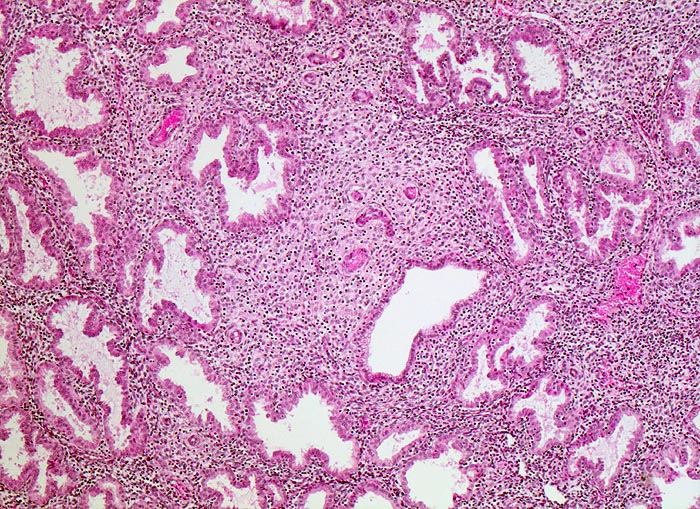

PathoPic ID 4745 - Sekretionsphase 10. Tag nach Ovulation

Sekretionsphase 10. Tag nach Ovulation

Endometrium

Genitalorgane, weiblich

Grosszellige Stromaumwandlung vor allem um die

Spiralarterien. Geschlängelte Drüsenschläuche mit Epithelknospen.

Dyspareunie

Vergrösserung

50

Alter